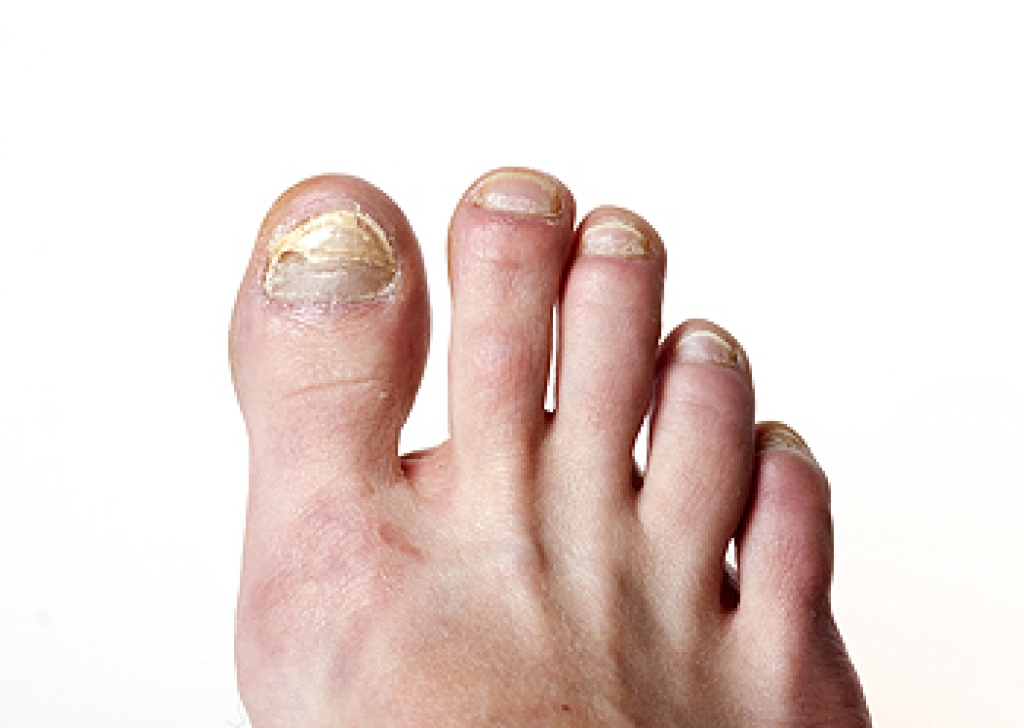

Hammertoes are a common deformity in which the second, third, fourth, or fifth toes bend downward at the middle joint. This gives the affected toes a hammer-like appearance. They may also be referred to as claw toes, mallet toes, or retracted toes. This deformity is said to be more common among people who have bunions or high arches. Wearing poorly-fitted shoes and socks that squish the toes together can exacerbate the problem as well. Hammertoes can be stiff and painful. Over time, the toe joints can lose their flexibility and you may be unable to straighten the toes without surgical intervention. People with hammertoes also often notice corns and calluses forming at the tops of their toes, where the skin over the bent toes rubs against shoes. If you are suffering from hammertoes it is suggested that you seek the care of a podiatrist.

Hammertoe is a foot deformity that affects the joints of the second, third, fourth, or fifth toes of your feet. It is a painful foot condition in which these toes curl and arch up, which can often lead to pain when wearing footwear.

- Pain in the affected toes

- Development of corns or calluses due to friction

- Inflammation

- Redness

- Contracture of the toes